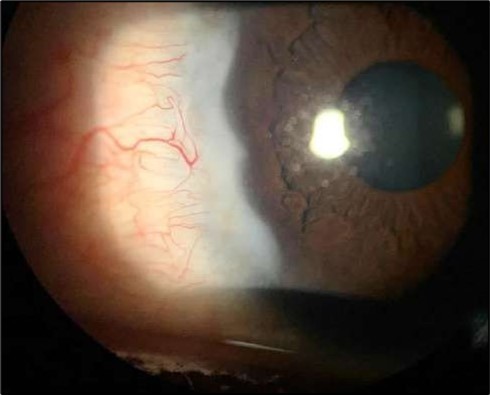

On the current presentation, Snellen VA was 6/6 in the right eye and 6/9 in the left eye, with normal IOP. The left eye demonstrated mild upper lid edema and intense nasal ciliary injection. Slit-lamp evaluation revealed a crescentic area of stromal corneal melting between 7 and 10 o’clock nasally, with overhanging edges and a fluorescein-positive base. No corneal infiltrates were present, and the surrounding stroma remained clear. The anterior chamber was deep and quiet, lens was transparent, pupil was round and reactive & normal posterior segment. Anterior segment optical coherence tomography (AS-OCT) confirmed a localized ulcer, measuring 1324 µm in horizontal width and extending to a depth of 380 μm, compared with an adjacent healthy corneal thickness of 824 µm, corresponding to approximately 46.1% stromal thinning (Figure 1a, Figure 1b, Figure 1c)

Figure 1a.Left eye (OS), on presentation. Slit-lamp image: crescent-shaped peripheral corneal ulceration located nasally, with severe adjacent conjunctival injection, peripheral thinning, and stromal infiltration.

At six-months follow-up post-resection, the ulcer showed progressive epithelialization with no recurrence. Oral prednisolone was gradually tapered and stopped. The patient remains under regular ophthalmology follow-up with stable ocular findings Figure 6.

Figure 6.Six-month follow-up image showing a stable ocular surface, and absence of ulcer recurrence. The cornea appears clear centrally, with stromal scarring limited to the periphery.